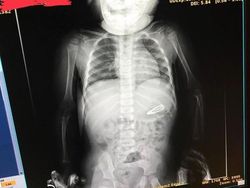

Ada-ada saja,anak gadis ini menelan jepitan rambut. (Foto: Brightside)

"Putriku menolak untuk melakukan X-ray tanpa Peppa Pig (boneka)," kata ayah gadis yg dipindai ini. Foto: Brightside